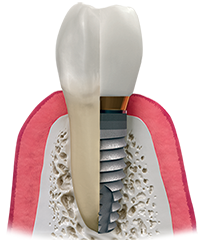

The fundamental for contemporary dental implants is a biological procedure known as osseointegration where high-quality material, say for instance titanium builds an intimate bond to the bone. The dental implant, usually a cylindrical and/or tapered post made of titanium, is placed surgically into the jawbone. As you heal, your implant will osseointegrate, or fuse with, your natural jawbone, with the two growing together to form a strong and long-lasting foundation for your replacement teeth. This healing process can take weeks to months while you proceed with your everyday life in between appointments.

Once the implant bonds with the jawbone, a small connector – called an abutment – is placed on top of the dental implant to connect the implant to the replacement tooth or teeth. An individual tooth, an implant-supported bridge or dentures containing multiple teeth are then attached to the abutment.